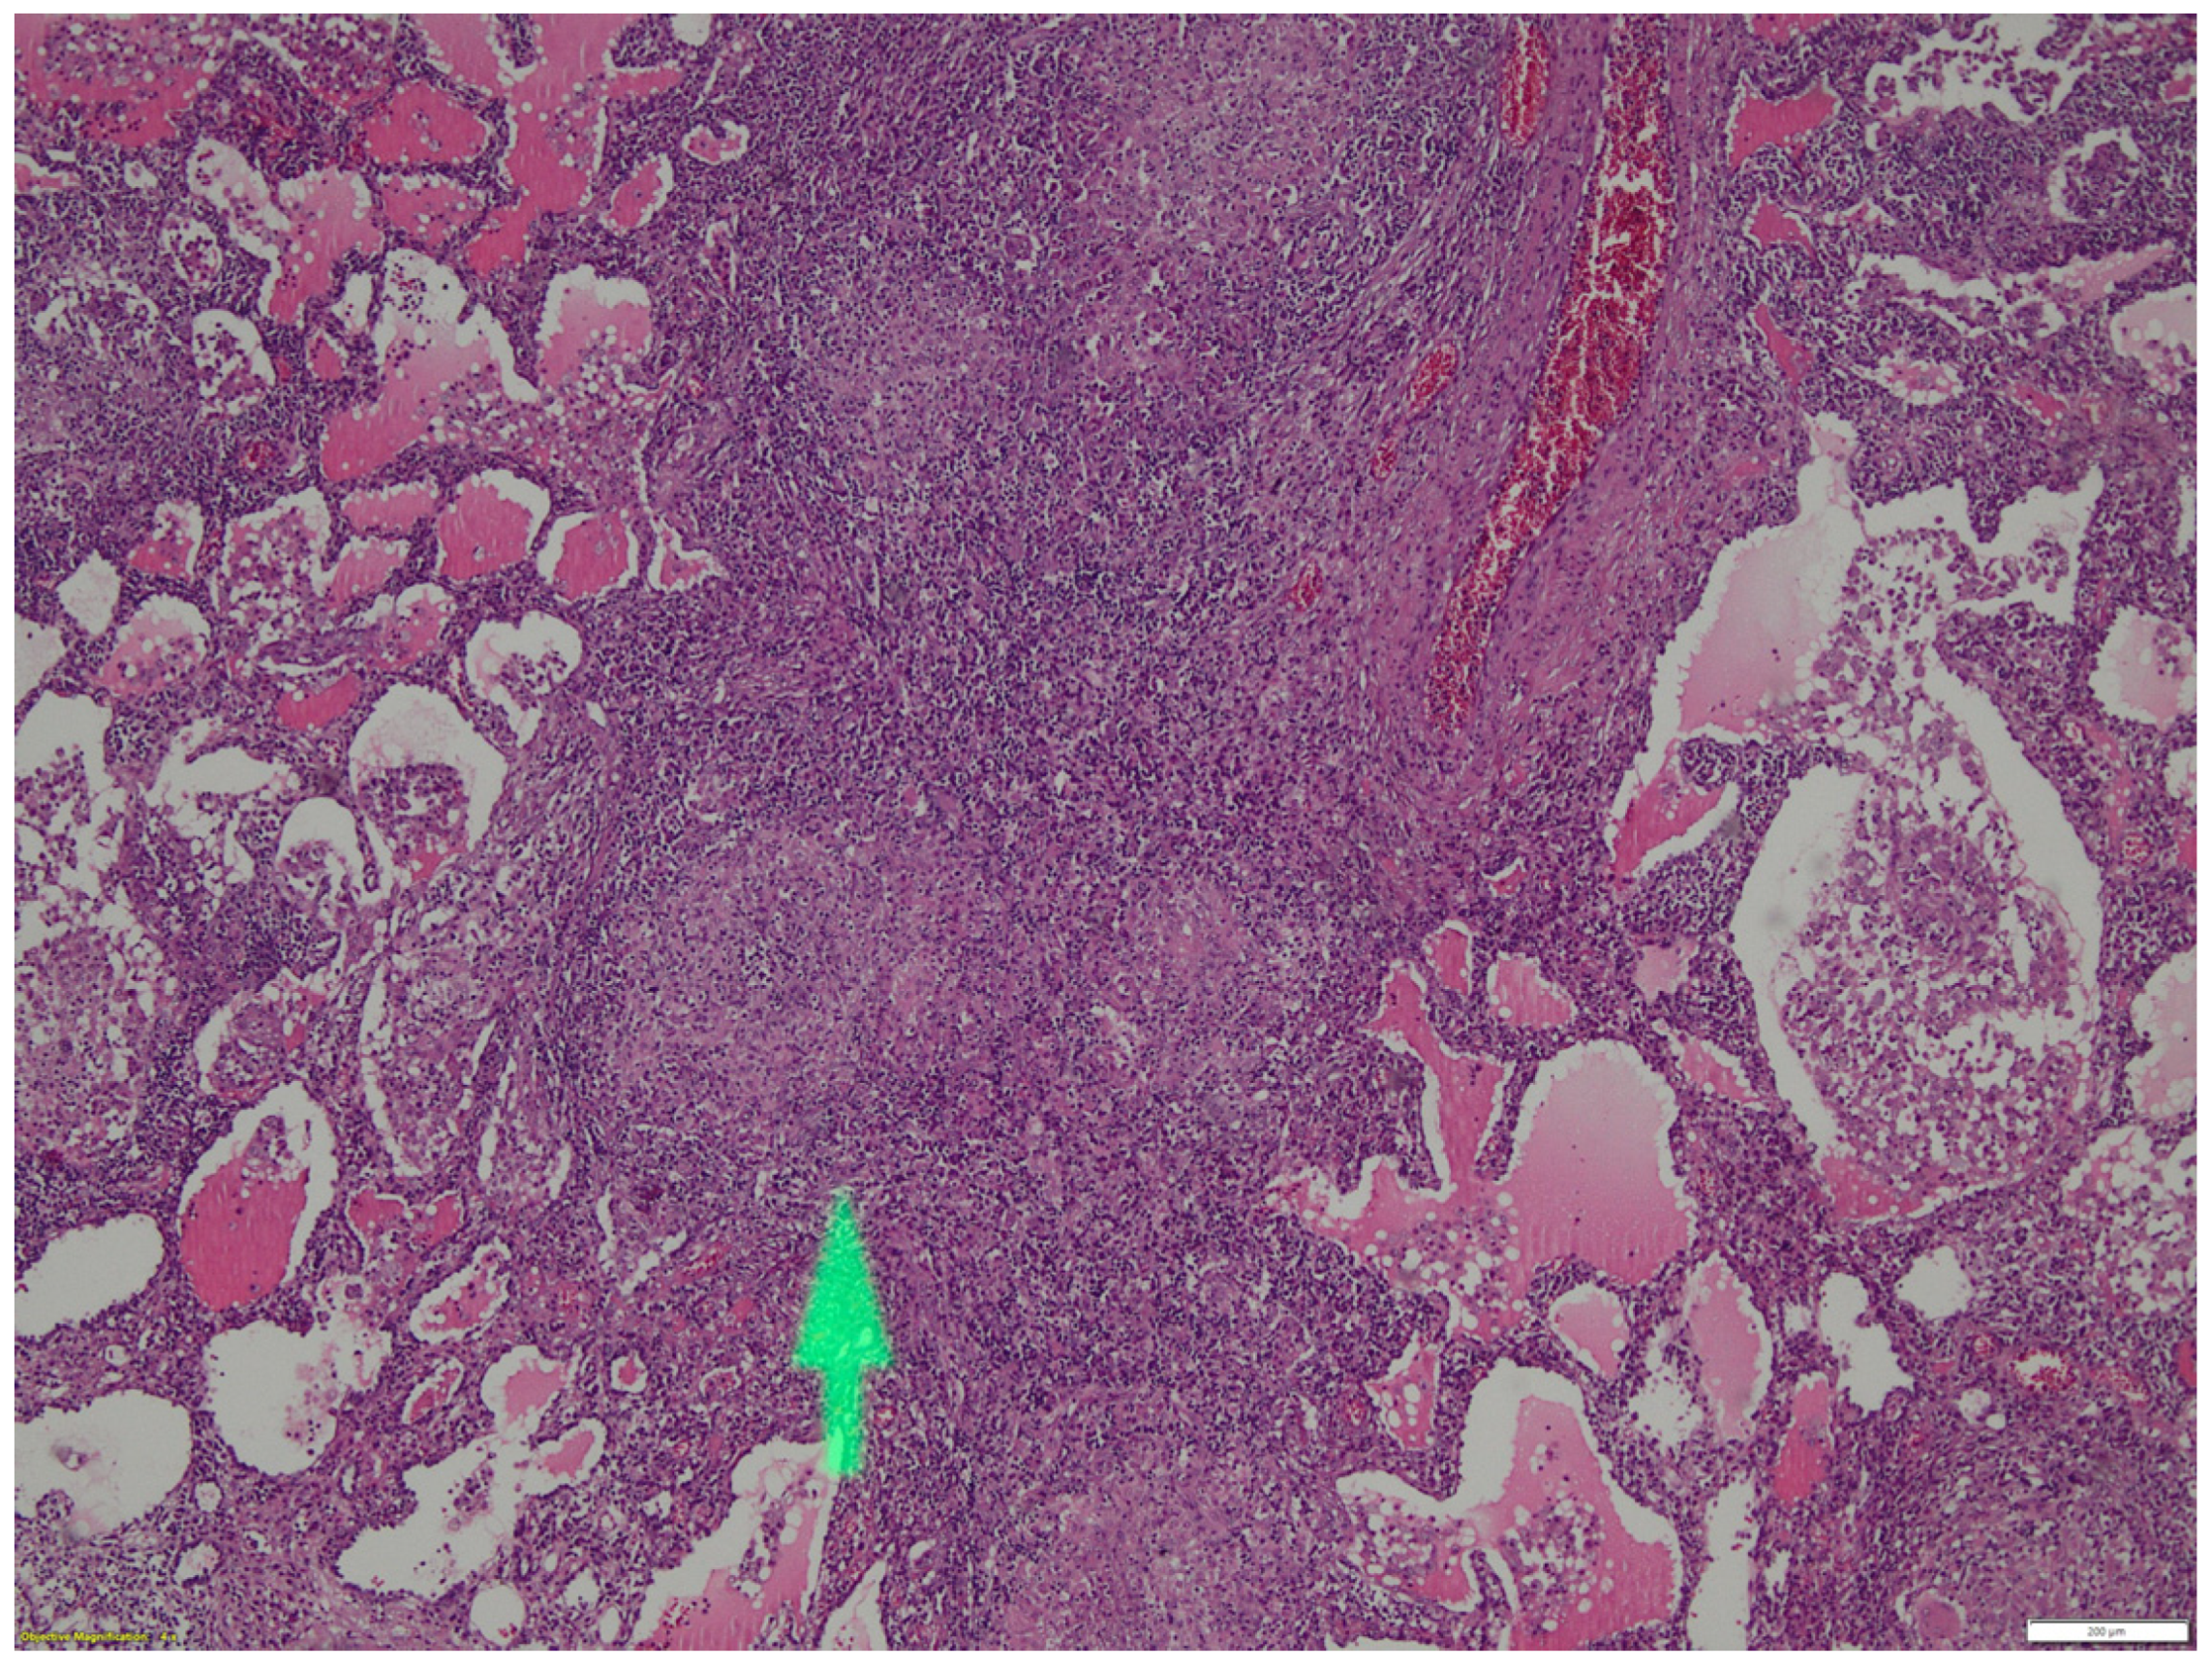

2. Case Report